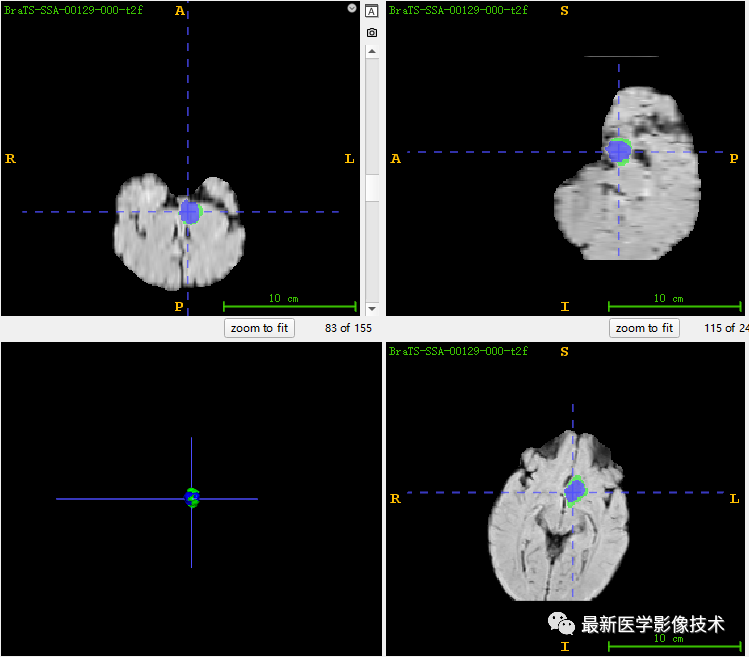

7、测试集分割结果